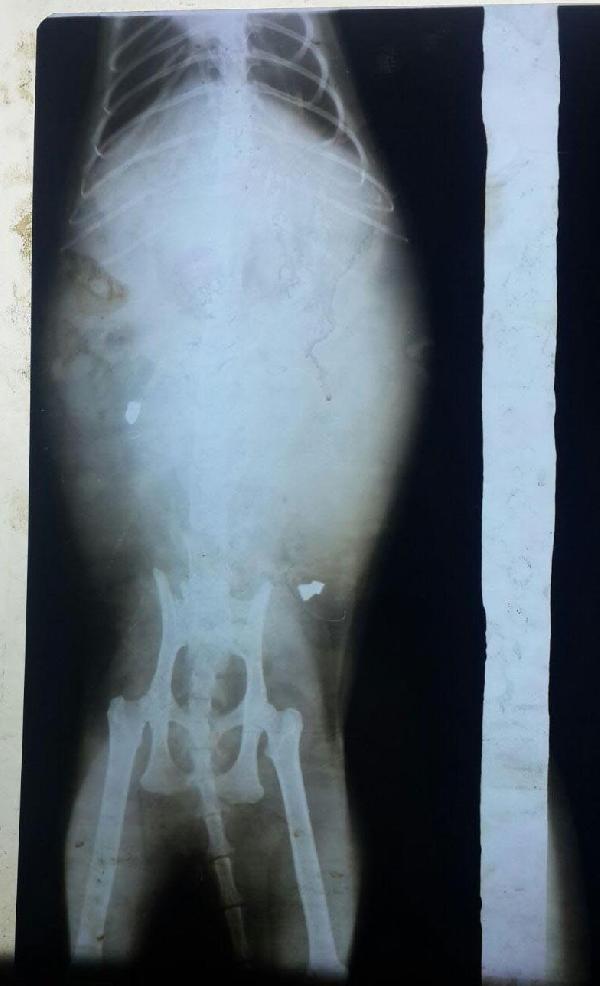

Aytül Kayserili'nin komşusu tarafından hemen veterinere götürülen Lea'nin çekilen röntgeninde, omiriliği delip geçerek yumuşak dokuya saplanan iki saçma tespit edildi. Olayı öğrenince büyük üzüntü yaşayan Kayserili, sosyal medyadaki, Çeşme- Alaçatı Sokak Hayvanları ve Barınağı Yardımlaşma Platformu'nda bir paylaşım yaparak şu sözlere yer verdi:

"Bu mahallede başımıza ikinci kez geliyor. Daha önce nedense sadece erkek köpekler havalı tufek ile vurulmuştu. Seneler geçti, 'Artık olmuyor' diye düşünüyorduk ki benim evimde doğup büyüyen canım kedim Lea'm bugün ben yokken, maalesef vurulmuş ve belden aşağısı tutmuyor. Allah'tan karşı komşum, Lea'yı benim duvarıma tırmanmak isterken görüp, hemen veteriner hekime götürmüş. Önce köpek ısırığı sanıldı. Ama çekilen röntgende, omurgayı kırarak giren, yumuşak dokuda olan iki adet saçmayı gördük. Söylenecek çok şey var, ama maalesef yapacak hiçbir şey yok. Tek umudum tedavinin işe yaraması. Onlar, en az evlat gibi seviliyor, önemseniyor. Onlar beni hayata bağlıyor. Sevgimi en çok onlar hak ediyor." (DHA)